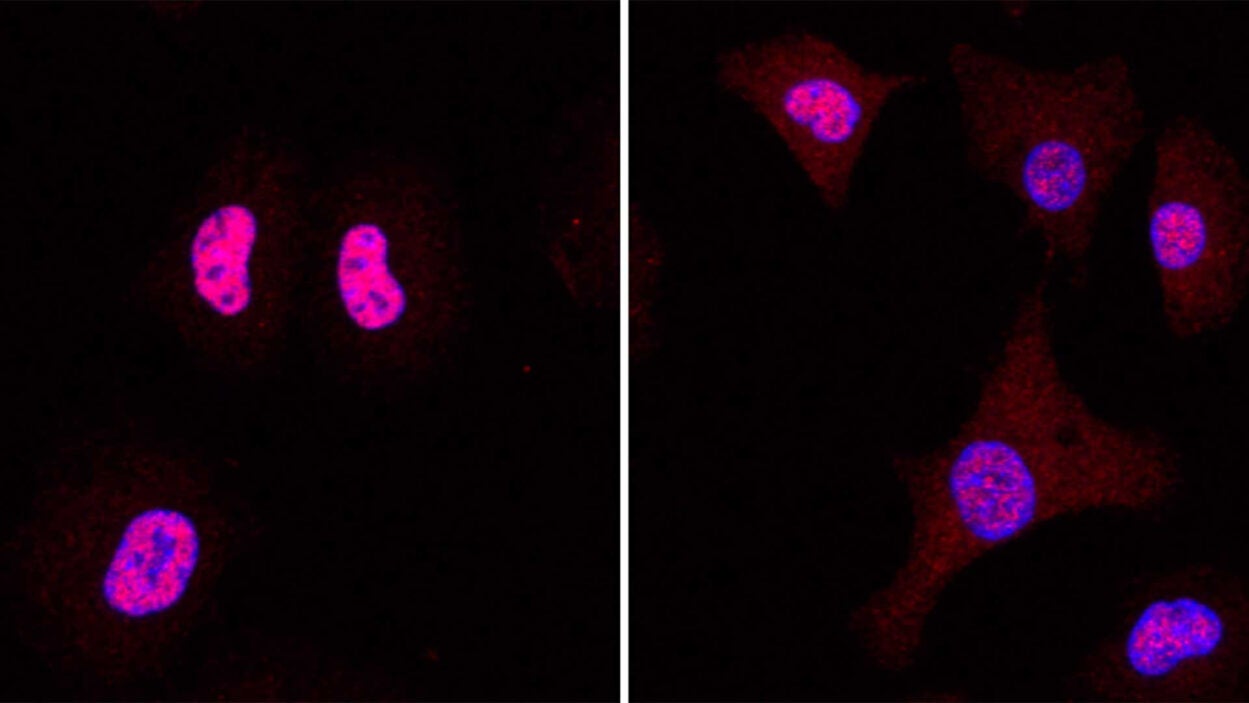

Research from new CSHL Assistant Professor Katherine Alexander suggests that nuclear speckles could influence kidney cancer patient outcomes. Read the story »

Her team will explore mysterious cellular structures known as nuclear speckles and their role in diseases such as cancer. Read the story »

Speckles sound innocent enough, like little spots. But don’t be fooled. These tiny structures could someday have big implications for cancer care. Listen to the podcast »

What are nuclear speckles and how might these mysterious structures impact your DNA? Get an inside look from CSHL Assistant Professor Kate Alexander. Watch the video »